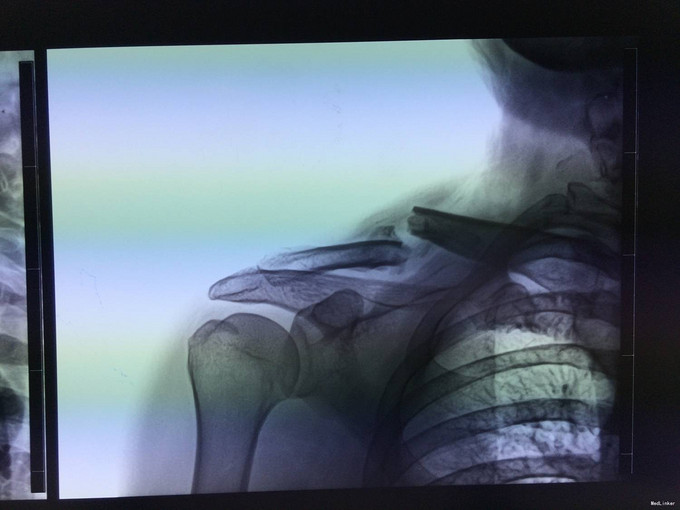

主诉:骑车摔伤后右肩部疼痛肿胀4小时 现病史:患者及家属自诉于2013年6月22日上午9点骑自行车摔倒致右肩部疼痛,肿胀,活动受限,当时无意识不清,到新民市当地医院,行X线片检查示:右锁骨骨折,未行治疗。现患者为求进一步治疗来我科,以“右锁骨骨折”为诊断收住入院。伤来患者无头痛及发热,无咳嗽咳痰,无腹痛及恶心呕吐,饮食睡眠可,大小便正常。

专科查体:右上肢吊臂带固定中,右肩部轻微肿胀,右锁骨处压痛(+),活动受限,骨擦感存在,右上肢无明显麻木,桡尺动脉清楚,各手指活动无受限。